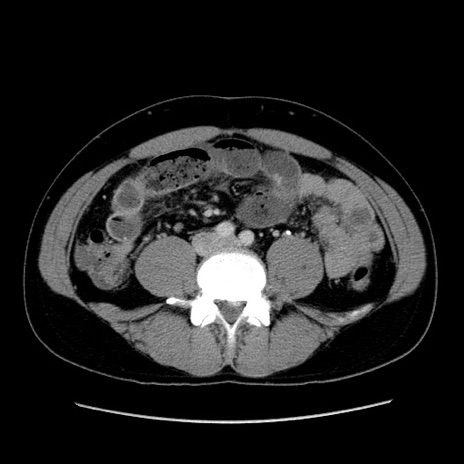

冠状断像

【症例】30歳代男性

【主訴】腹痛、嘔吐

【現病歴】昨晩から突然の腹痛あり、その後嘔吐、軟便も出現。腹痛が改善しないため救急搬送となる。2日前にしめ鯖の食事歴あり。

【身体所見】意識清明、苦悶様、BP 135/90mmHg、BT 35.7℃、腹部:平坦、やや硬、心窩部〜臍部に自発痛、圧痛あり、筋性防御+、反跳痛-

【データ】WBC 8100、CRP 0.57